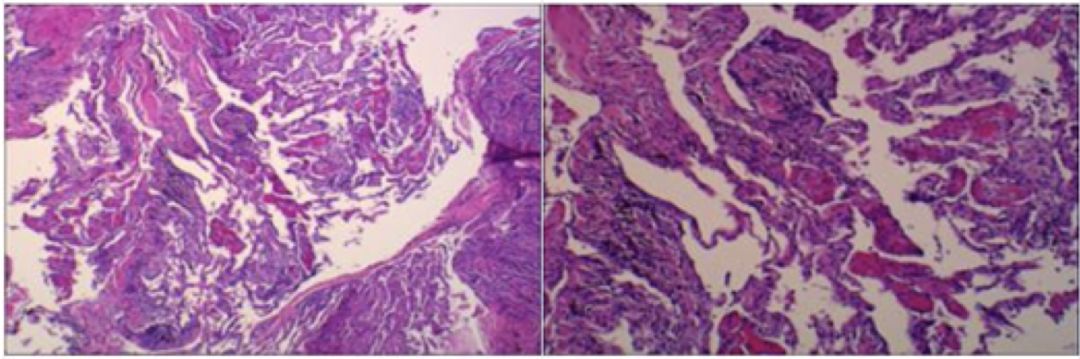

(呼吸与危重症医学科)需要强调的是,病理学发现肺泡腔内有纤维素渗出不等同于机化性肺炎。纤维素渗出可以见于细菌感染、弥漫性肺泡损伤、见于OP及嗜酸性粒细胞肺炎。但该患者TBLB病理结果局部发现机化及肺泡腔内纤维素渗出,可以认定病人存在机化性肺炎。

隐源性机化性肺炎是特发性间质性肺炎的一个亚型,临床表现上难以与普通肺炎相区别,但有其独特的影像学特征,主要表现为多形性、多态性、多变性,该患者影像学特征是符合COP的。COP的病理学特征是肺泡腔内由肉芽组织充填伴有纤维素渗出,但纤维素渗出往往不超过10%。AFOP是2013年间质性肺病中提出的一种特殊的病理类型,可以分为特发性和继发性,继发因素与SOP相似,特发性又分为2类,急性与亚急性,急性的发病迅速,很快进展至呼吸衰竭,亚急性在病程在病程上类似OP,但亚急性AFOP是否是一种独立的疾病,很多学者还存在争议。GOP是一种新近发现的机化性肺炎,同样以肺泡腔机化为主,但肺泡腔内炎症细胞以淋巴细胞和浆细胞浸润为主,在临床上更为罕见。间质性肺疾病的诊断依赖于临床、影像、病理多学科协作,该病人临床特点及影像学特征符合COP与亚急性AFOP,但定性需要依赖病理学对肺泡腔内纤维素渗出比例的判读,如纤维素渗出比例小于10%,在排除继发因素的前提下,可考虑COP;如纤维素比例超过50%,甚至形成纤维素球,则考虑AFOP可能性大,结合患者病程特点亚急性起病,则考虑亚急性AFOP。

李道明教授

(病理科)患者肺穿刺病理结果与TBLB病理结果还是有很大区别,TBLB病理结果最突出的病变是间质性肺炎,肺泡里面有少量红染的纤维素样渗出物,而右下肺穿刺病理结果间质性肺炎不明显,肺泡壁增厚不明显,最突出的病变为肺泡腔内大量红色纤维素样渗出物,有些通过肺泡间孔相连,切片上有些地方镜下可见纤维母细胞和肌纤维母细胞增生(即肉芽组织)以及炎症细胞浸润。

肺穿刺的病理结果诊断机化性肺炎是没有问题的。机化性是病理现象,不能作为一种独立性疾病进行诊断,是疾病伴发的一种现象。SOP和COP镜下较难区分,但AFOP和COP的区别则主要看纤维素渗出的量,该患者肺穿刺病理从整体切片来看纤维素渗出的量在30~50%之间,未见多核巨细胞及中性粒细胞及嗜酸性粒细胞浸润,以少量淋巴细胞及少量单核细胞浸润为主。综上所诉,诊断AFOP较为合理,同时需进一步结合临床。

(呼吸与危重症医学科)经过临床、影像与病理综合分析,该患者最终诊断为亚急性纤维素性机化性肺炎。AFOP是2013年由美国胸科协会与欧洲呼吸协会发布的特发性间质性肺疾病的一个类型,发病年龄通常在50-70岁,男性发病率略高于女性,可分为特发性和继发性,临床表现可出现全身性及呼吸系统症状,病人可出现发热、胸闷、呼吸困难、咯血等。该病临床类型分为急性爆发型和亚急性2种类型,急性爆发型病情进展迅速,病人很快进展至ARDS,平均死亡时间为29天,死亡率高达90%。亚急性型病程大于2个月,该病人临床特点符合亚急性,亚急性预后较好,影像学表现可表现为多发斑片影、渗出影,结节影、可出现游走性,类似于COP影像学特点,但最终要有赖于病理诊断。AFOP病理学特征为肺泡腔出现纤维素沉积,无肉芽肿形成,无透明膜形成,无嗜酸粒细胞浸润,这一点需要与COP鉴别。OP的病理学特征为肺泡腔内可见肉芽肿形成,即肌纤维细胞和成纤维细胞,该点要与AFOP进行鉴别。